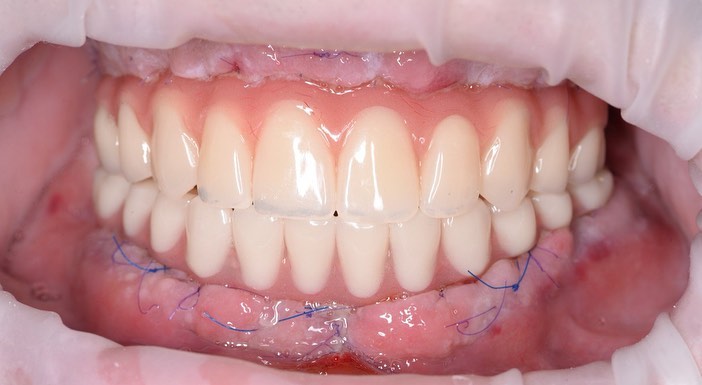

Тотальная имплантация AnyOne методом all-on- 4.

Иващенко Александр Николаевич: клинический стоматолог-хирург, практикующий имплантолог.